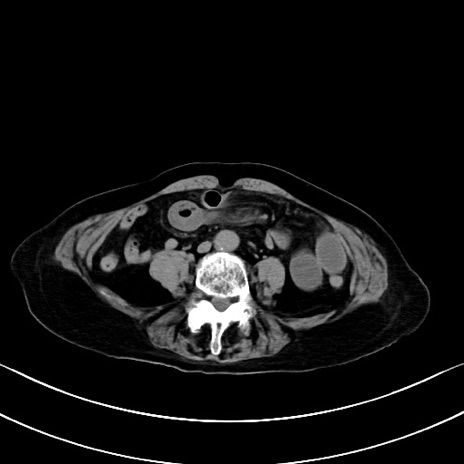

症例40(横断像)他院1日前

横断像

他院CT